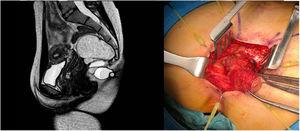

Ultrasound and pelvic magnetic resonance imaging identified a multilobulated mass with well-defined borders adjacent to the rectum, which extended outside the pelvic cavity through a midline defect that was caudal to the sacrum, compatible with a retrorectal cystic hamartoma with extrapelvic extension. The lesion was excised using an abdominosacral approach, and the pathological study confirmed the diagnosis (Fig. 1).

Please cite this article as: Gómez Sánchez J, Zurita Saavedra M, Gutierrez Sainz J, Mirón Pozo B. Hamartoma quístico retrorrectal con componente extrapélvico. Cir Esp. 2021;99:230.